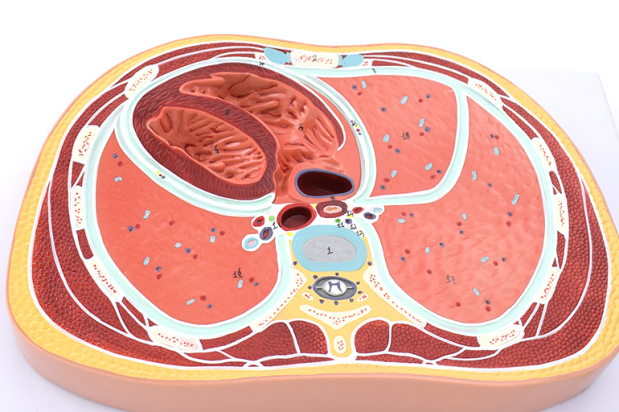

贵州航天医院呼吸团队借助AI机器人智能影像分析、穿刺计划系统,对患者肺结节进行了多视角的立体三维重建,精确定位了病灶,并规划出最佳进针位置、角度和轨迹,通过AI机器人可视影像系统和机械臂穿刺系统的引导,“一针”就穿刺进入病灶预定位置进行冷冻消融,手术仅30分钟,患者安返病房。

AI机器人辅助消融治疗术是一种较为先进的精准、微创技术,医生通过AI机器人精密的操作系统,以毫米级的精确度操控冷冻或微波探针,直达靶点,释放低温或高温摧毁病变组织,同时明显提升了手术的安全性和效率。

氩氦刀冷冻消融是通过将一根1.7-3毫米的中空钢针,穿刺进入病灶,先注入氩气,迅速降温至-160摄氏度左右,冰冻肿瘤数分钟,再注入氦气,快速升温至20-30摄氏度,让肿瘤细胞在短时间内冷冻及复温,对病灶组织进行物理性杀灭。